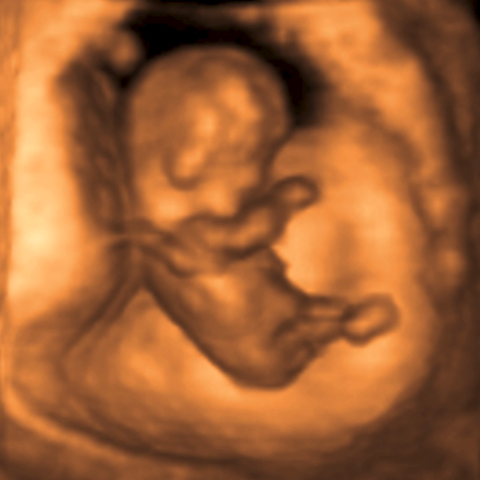

1st trimester pregnancy [3 of 3]